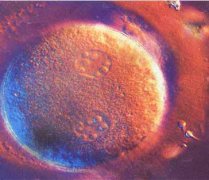

怀孕一个月胎儿彩超图片如下:

怀孕一个月胎儿彩超图片